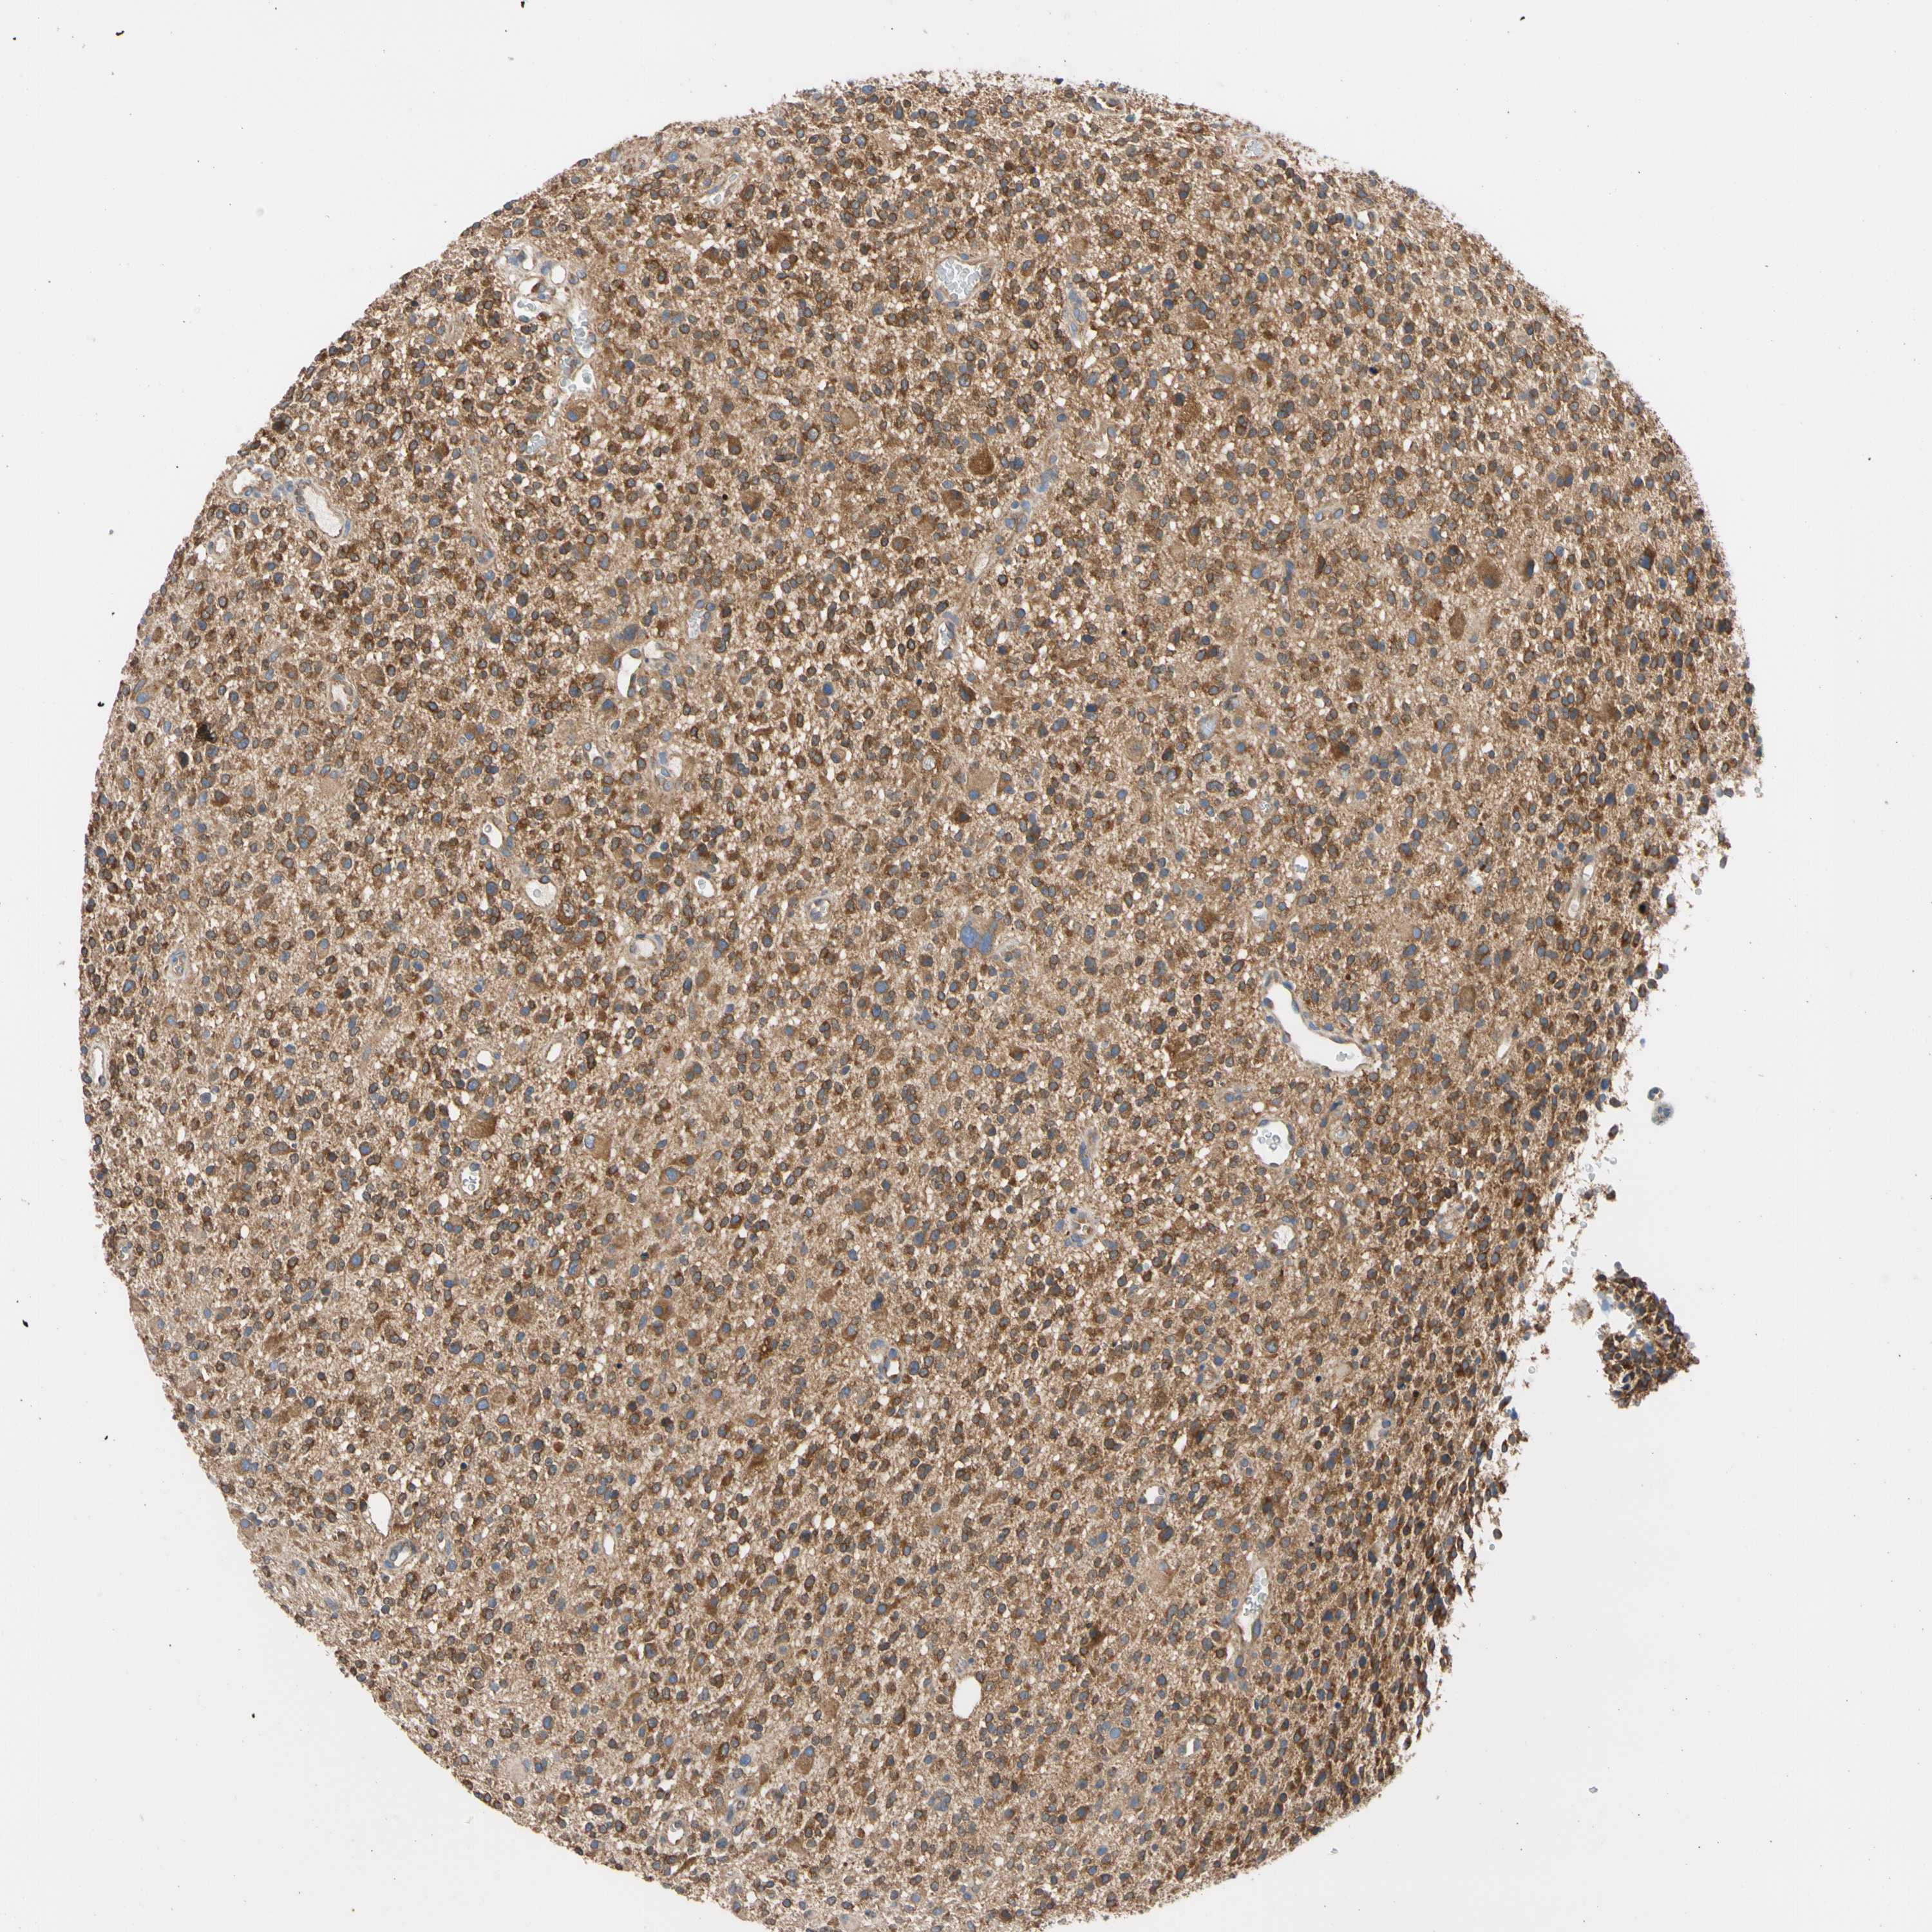

GLIOMA - Protein expressioni

A mouse-over function shows sample information and annotation data. Click on an image to view it in a full screen mode. Samples can be filtered based on level of antibody staining by selecting one or several of the following categories: high, medium, low and not detected. The assay and annotation is described here.

Note that samples used for immunohistochemistry by the Human Protein Atlas do not correspond to samples in the TCGA dataset.

Antibody stainingi

Antibody staining in the annotated cell types in the current human tissue is reported as not detected, low, medium, or high, based on conventional immunohistochemistry profiling in selected tissues. This score is based on the combination of the staining intensity and fraction of stained cells.

Each image is clickable and will lead to virtual microscopy that enables deeper exploration of all samples and also displays staining intensity scores, fraction scores and subcellular localization as well as patient and tissue information for each sample.

Antibody HPA003116

Antibody HPA024694

Antibody CAB004419

Staining

High

Medium

Low

Not detected

Intensity

Strong

Moderate

Weak

Negative

Quantity

>75%

75%-25%

<25%

None

Location

Nuclear

Cytoplasmic/membranous

Cytoplasmic/membranous,nuclear

Glioma, malignant, High grade

Glioma, malignant, Low grade